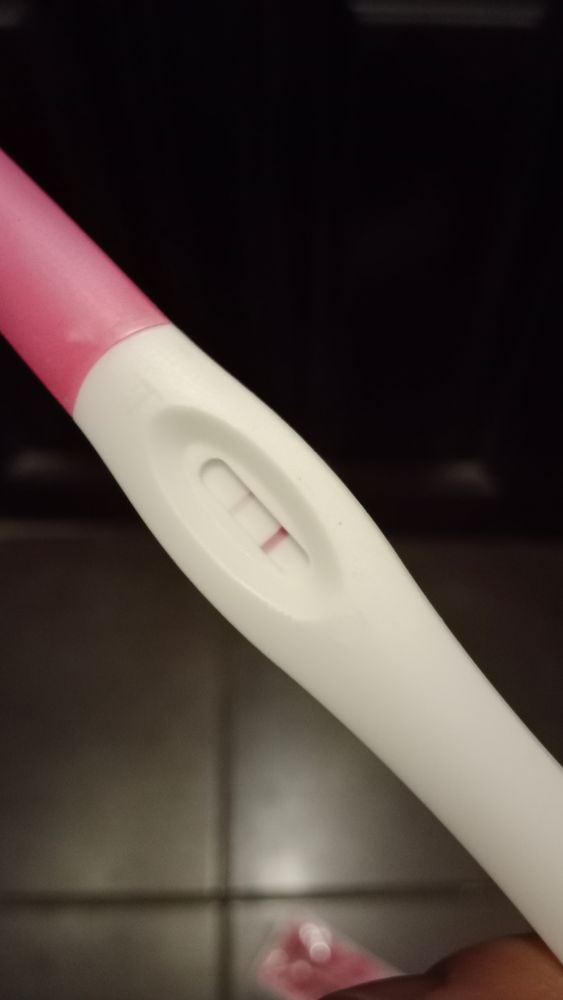

Слабовата? Врет?

Суть. Цикл 27 дней До задержки тесты пустые

На 4 и 5 день фрау пустые

Сегодня 9 день задержки тест феми струйный.

Врет?